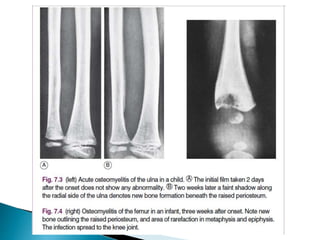

• 1st 10 days Show No Abnormality .

Only after two or three weeks do visible changes appear, and they

may never do so if efficient treatment is started very early.

• By the end of the 2nd Week signs of rarefaction of

Metaphysis and New Bone Formation. Then sigs of

healing

• Soft-tissue edema at 1-3 days after start of infection.

• Bony changes are not evident for 14-21 days:

– Early radiographic signs of rarefraction (thining of

bony tissue sufficient to cause decreased density of

bone) of the metaphysis and new bone formation

outlining the raised periosteum